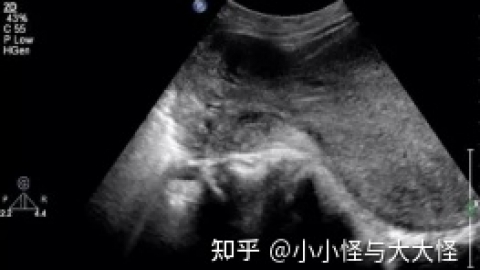

巧克力囊肿的检查方法都有哪些?B超对巧克力囊肿的诊断意义非常大。腹腔镜是目前诊断巧克力囊肿可靠的方法,借助腹腔镜直接窥视盆腔,可对子宫内膜异位范围及卵巢改变情况做出详细准确的评估,同时可对巧克力囊肿进行治疗。都可以作为卵巢巧克力囊肿的辅助检查诊断手段。巧克力囊肿会随着时间的发展逐渐加重,影响女性生育,降低生活质量,所以检查确诊巧克力囊肿就要及时的治疗。